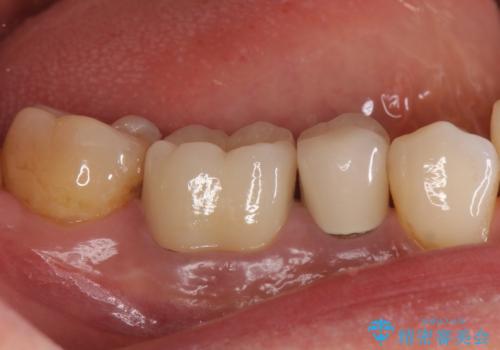

目立つ銀歯を白くしたい ジルコニアクラウンでの修復

気になっていた銀歯を自然な色に変えることができ、大変喜んでいただけました。

- 天然歯を削ります

- 硬い素材は天然歯を傷つけてしまう場合があります

- かみ合わせや歯ぎしりが強すぎる方はセラミックが割れてしまう可能性があります